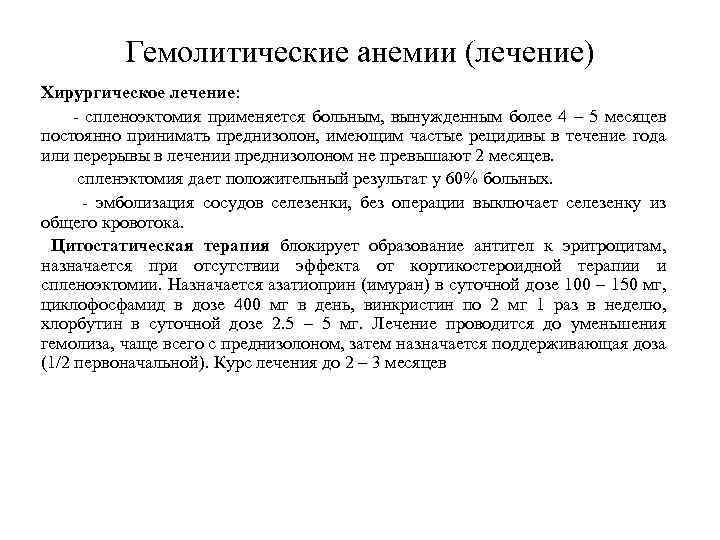

Гемолитические анемии (лечение) Глюкокортикоидная терапия. - при острых формах назначается преднизолон в дозе 60 – 80 – 150 мгсут и более. Суточная доза в 3 приема в пропорции 3: 2: 1. - по мере уменьшения проявлений криза доза постепенно снижается по 2. 5 – 5 мг в день до половины исходной. Далее она снижается на 2. 5 мг каждые 4 – 5 дней, затем еще меньшими дозами с большими интервалами, после чего отменяют. - при хронической аутоиммунной гемолитической анемии с неполными тепловыми агглютининами преднизолон применяют в суточной дозе 20 – 40 мг, а затем – поддерживающая доза (5 – 10 мг в день). Лечение эффективно у 80% больных, но рецидивы наступают часто. При хронической аутоиммунной гемолитической анемии с неполными тепловыми агглютининами преднизолон применяют в суточной дозе 20 – 40 мг, а затем – поддерживающая доза (5 – 10 мг в день). Лечение эффективно у 80% больных, но рецидивы наступают часто. - применяют иммунодепрессанты - хлорбутил, - плазмаферез, - иммуноглобулин G 0. 5 – 1 г/кг/сут в/в в течение 5 суток

Гемолитические анемии (лечение) Хирургическое лечение: - спленоэктомия применяется больным, вынужденным более 4 – 5 месяцев постоянно принимать преднизолон, имеющим частые рецидивы в течение года или перерывы в лечении преднизолоном не превышают 2 месяцев. спленэктомия дает положительный результат у 60% больных. - эмболизация сосудов селезенки, без операции выключает селезенку из общего кровотока. Цитостатическая терапия блокирует образование антител к эритроцитам, назначается при отсутствии эффекта от кортикостероидной терапии и спленоэктомии. Назначается азатиоприн (имуран) в суточной дозе 100 – 150 мг, циклофосфамид в дозе 400 мг в день, винкристин по 2 мг 1 раз в неделю, хлорбутин в суточной дозе 2. 5 – 5 мг. Лечение проводится до уменьшения гемолиза, чаще всего с преднизолоном, затем назначается поддерживающая доза (1/2 первоначальной). Курс лечения до 2 – 3 месяцев